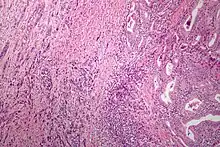

Elle est principalement observée dans les proliférations tumorales malignes où le degré de différenciation peut être faible ou nul. On parle alors de tumeur indifférenciée ou anaplasique[1]. L’anaplasie est donc la perte anormale de certains caractères de différenciation cellulaire, sans pour autant qu’il y ait un véritable retour à l'état de cellule primaire[3].

Les cellules anaplasiques se divisent rapidement et tant leur aspect que leur fonctionnement ne ressemblent plus à celui des cellules normales de l’organe concerné[2],[4]. Plus l'anaplasie est importante, plus la tumeur est jugée maligne et le pronostic mauvais[3].